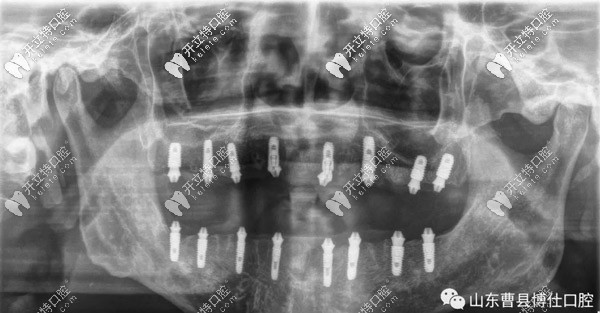

經(jīng)過一個半小時的手術(shù)時間,徐大爺上頜和下頜各植入8顆種植體,縫合傷口后,拍片顯示植入位置非常好。

通過拍片顯示,臨時牙和螺栓結(jié)合非常緊密,不需要調(diào)整,也經(jīng)過多次的反復(fù)咬合之后,并沒有不適的情況。